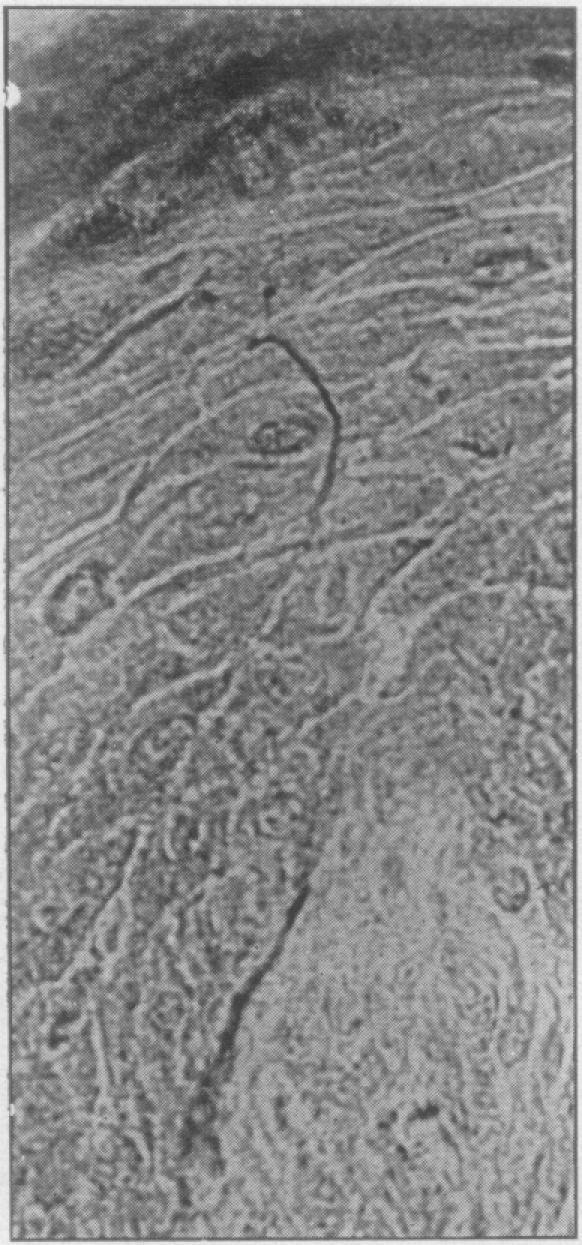

A comparative study of the innervation of the epithelium of the gum.

Proc R Soc Med. 1946 Apr;39(6):348-54. doi: 10.1177/003591574603900629.